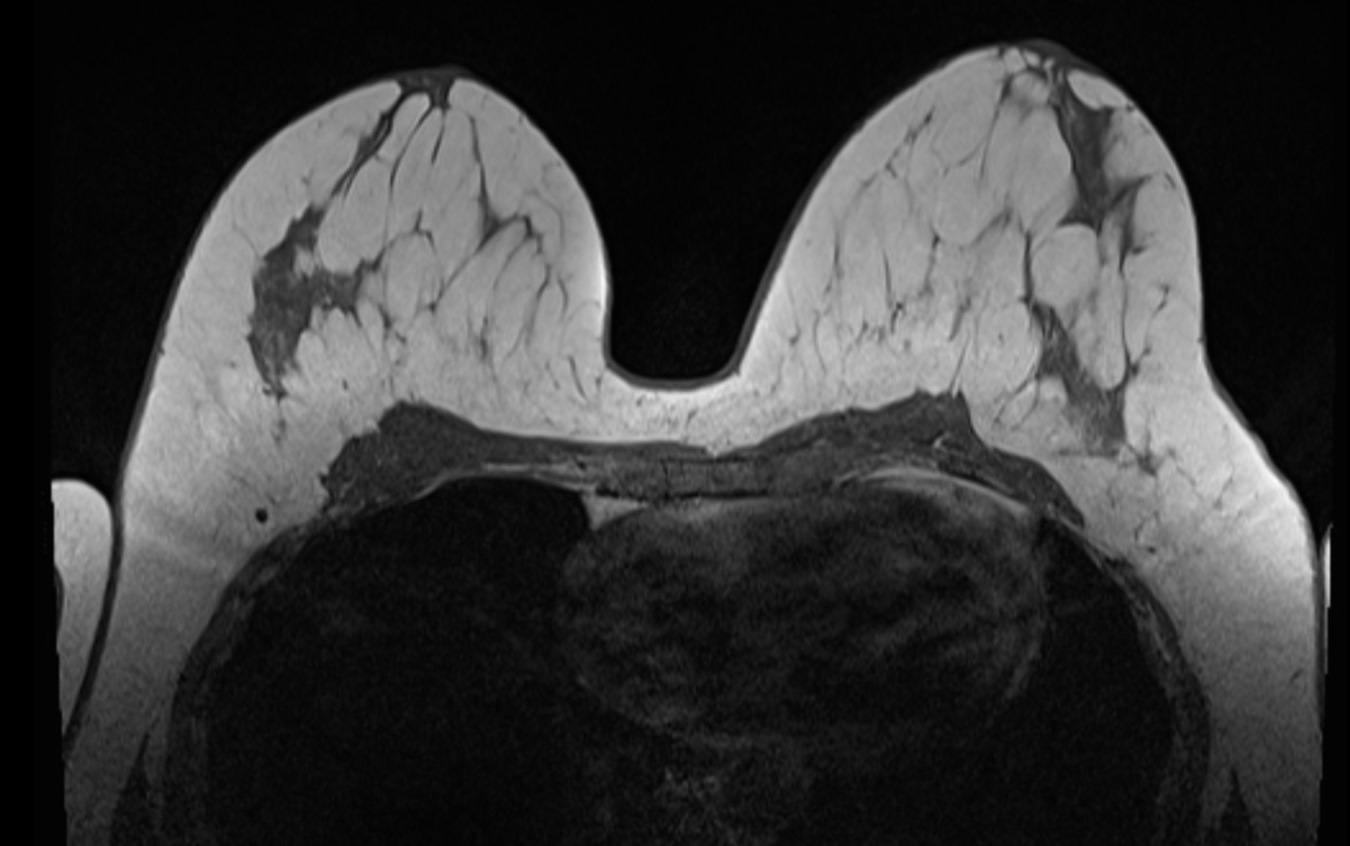

Checkliste für Ihre MRT-Untersuchung

Bitte bringen Sie alle relevanten Unterlagen mit, damit wir Ihre Untersuchung sicher und reibungslos durchführen können. Eine kurze Vorbereitung hilft, den Ablauf für Sie so angenehm wie möglich zu gestalten.